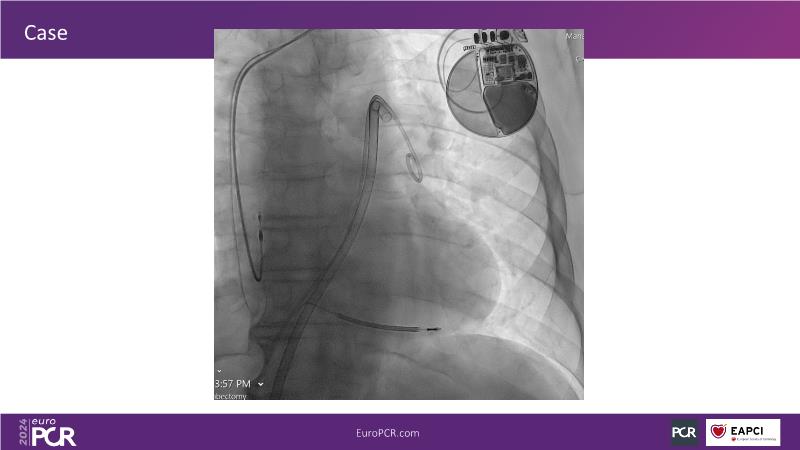

Advancing percutaneous treatment of pulmonary embolism with computer-assisted vacuum thrombectomy

Join this session to delve into innovations in computer-assisted vacuum thrombectomy for acute pulmonary embolism, leveraging real-life case scenarios to share practical experiences and discuss treatment strategies. Amidst the current surge in scientific research, ongoing trials like STORM PE and STRIKE PE are pivotal in shaping the landscape of pulmonary embolism management.